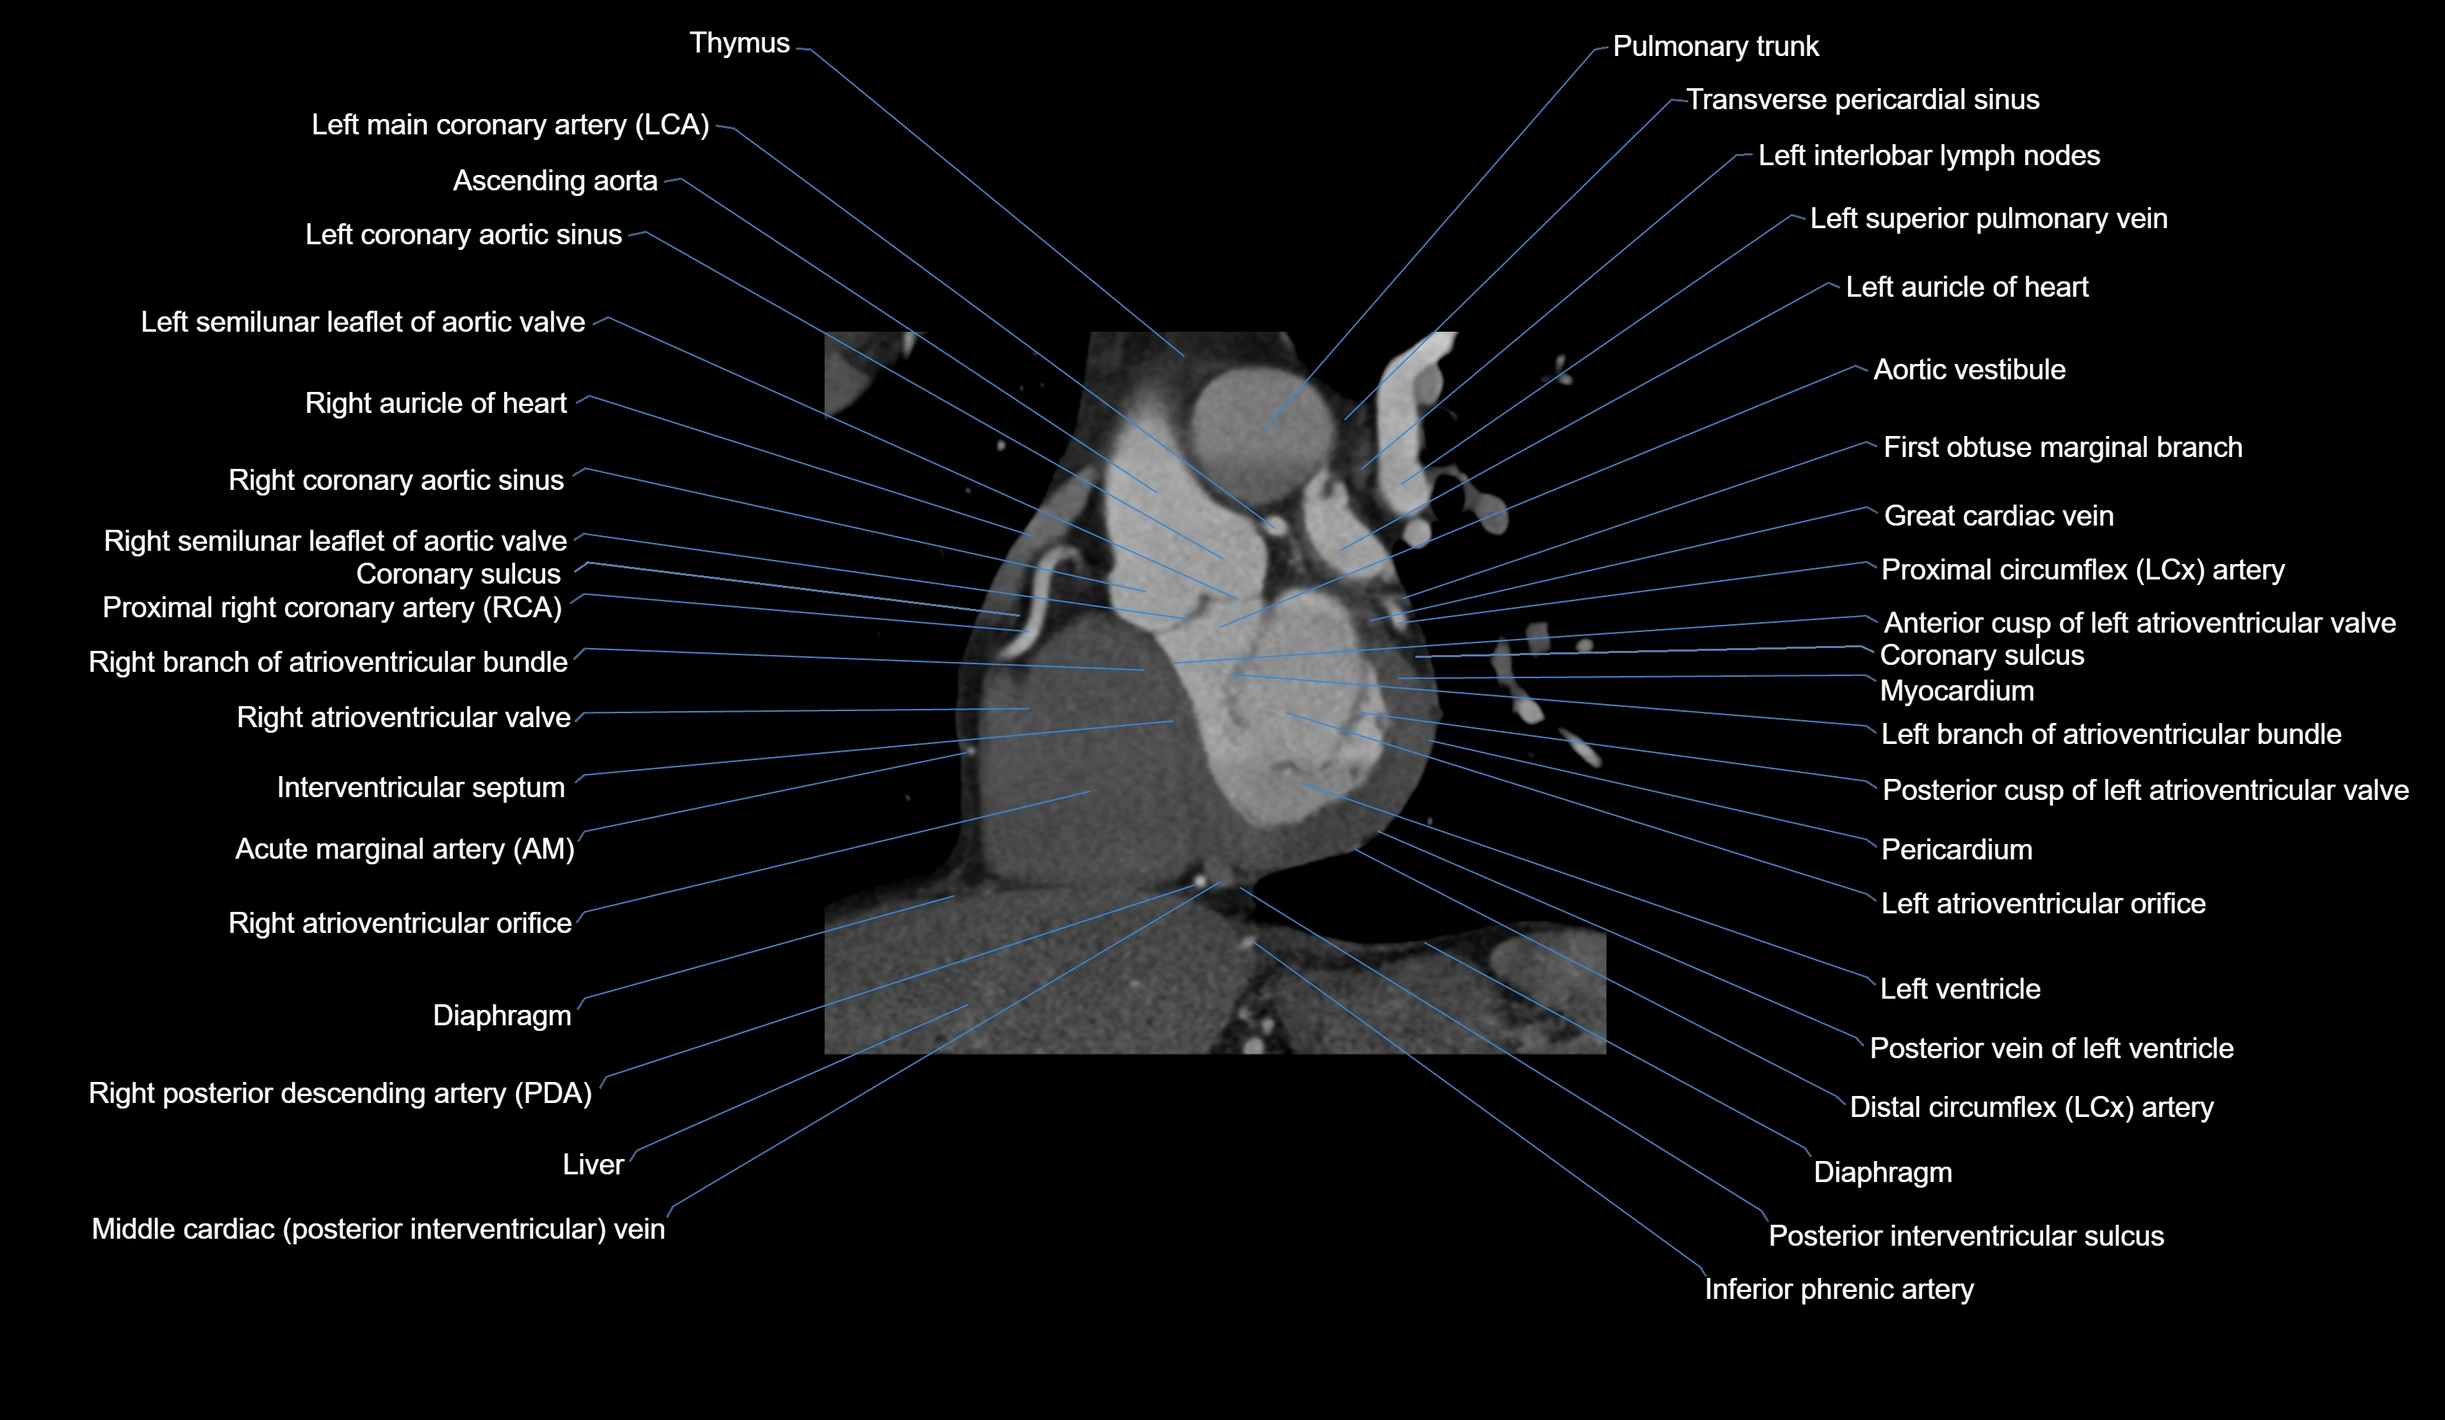

- Acute marginal artery (AM)

The acute marginal artery (AM) is one of the main branches of the right coronary artery (RCA). It typically arises from the mid to distal segment of the RCA and courses along the acute margin (right inferolateral border) of the right ventricle. The AM artery runs within the epicardial fat and supplies blood primarily to the right ventricular free wall.

The number and size of AM branches vary: most individuals have one dominant acute marginal artery, but some may have multiple smaller branches. The vessel is of high clinical importance in right ventricular infarction, since occlusion or disease of the RCA or AM branch can compromise right ventricular contractility and systemic venous return.

CT Coronary Angiography (CCTA):

-

Best non-invasive modality for acute marginal artery visualization

Shows origin, course along the acute margin, and right ventricular branches

Detects stenosis, occlusion, calcified and non-calcified plaques, aneurysm, or anomalous course

Multiplanar reformats and 3D reconstructions help in pre-PCI and surgical planning

Critical for assessing right ventricular infarction risk in RCA disease

CT images